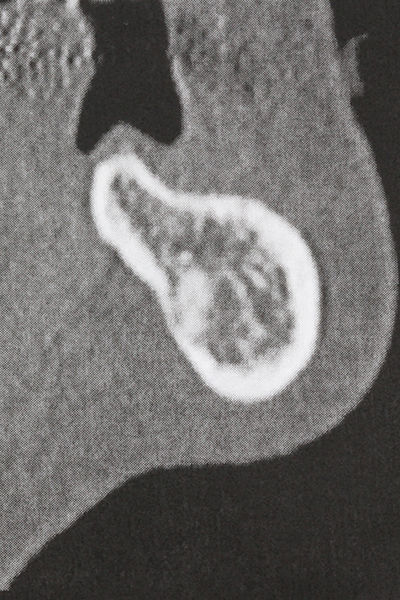

Indication: Preparation near nerves

When surgical procedures are performed on bone in the immediate vicinity of sensitive structures such as blood vessels or nerves, rotary instruments pose a significant risk of iatrogenic injury. Piezoelectric devices can be helpful for preparation of bone covers and removal of hard tissue close to nerves, particularly for exposure of nerves after iatrogenic injury but also during nerve lateralization for resective and reconstructive procedures or implant placement (Fig. 17-20). Light contact between the piezotip and the nerve does not generally result in damage but proceeding incautiously with saw-like motions or attachments where a residual bone substrate remains may cause temporary or even permanent nerve damage. However, the risk of damage is considered to be substantially lower than when using saws or milling instruments (Pereira, Gealh et al. 2014).